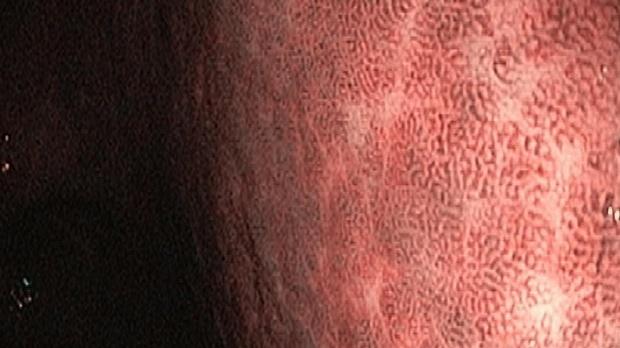

Появление ультратонких гастроскопов с высоким разрешением и технологией NBI (оптического узкоспектрального режима) компания OLYMPUS сделала возможной гастроскопию экспертного уровня под местной анестезией, без наркозных рисков.

Ультратонкие гастроскопы GIF-XP170N и GIF-XP190N с параметром оптики Close Focus, который позволяет приближаться к слизистой на минимальную глубину резкости до 2 мм, обеспечивают качество изображения, сопоставимое с аппаратами экспертного класса.

Использование в ежедневной рутинной практике современных ультратонких эндоскопов высокого разрешения с технологией оптического узкоспектрального режима (NBI® OLYMPUS™) под местной анестезией позволило полностью обеспечить соответствие критериям качества выполнения эндоскопических исследований, определенным ESGE. Данный метод комфортен для пациента под местной анестезией, безопасен, является простой и удобной альтернативой ЭГДС под седацией, что особенно важно в амбулаторных условиях.